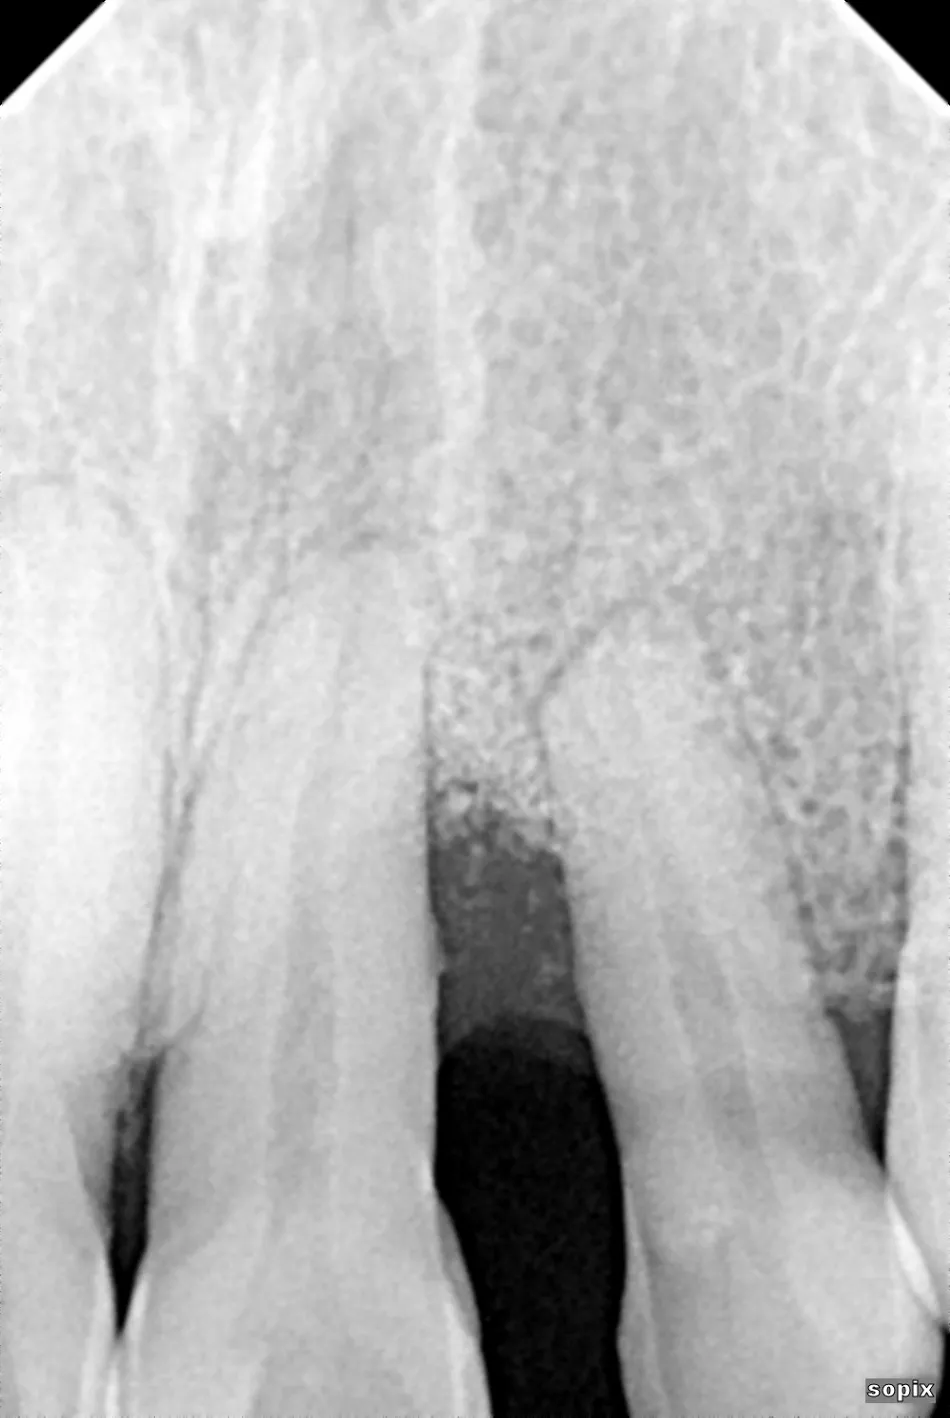

A 46-year-old male healthy (ASA I), non-smoker, with no medication, was referred to our practice for a papilla reconstruction in the anterior esthetic zone. The intraoral examination revealed a protruded and extruded tooth #22, localized erythema and edema at teeth #21 and #22, with a severe loss of the interproximal papilla. The periodontal examination revealed a PPD of 8 mm at teeth #21 and #22, and established a diagnosis of localized stage III, grade C periodontitis (Fig. 1). The radiographic examination revealed a severe vertical osseous defect (Fig. 2).

The patient paused his treatment due to the COVID-19 pandemic. The radiographic control two years after surgery revealed significant bone fill of the defect (Fig. 13), and the patient began orthodontic treatment.

Control at one year after the second surgery. The diastema between incisors was closed with controlled movements (Fig. 14). The radiographic control revealed an important interdental bone fill and periodontal stabilization of teeth #21 and #22 (Fig. 15).